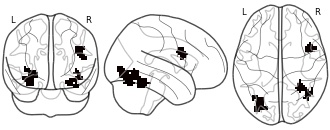

"name": "Multi_VBMsmaller_fMRIenhanced",

"description": "Multi-modal analysis in BPD. Brain regions exhibiting smaller gray matter and enhanced activation during emotion processing in BPD compared to healthy controls. Note: Results were thresholded at p<.0025. Note2: Results were updated (see Erratum for this publication).",